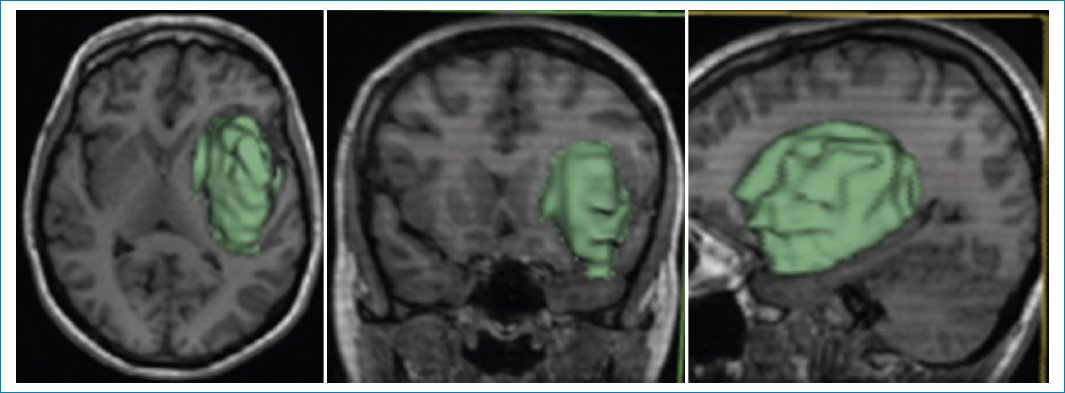

Las imágenes de resonancia magnética (RM) muestran una masa frontoinsular izquierda, hipointensa en la secuencia ponderada en T1 (Fig. 1), hiperintensa en T2 (Fig. 2) e hiperintensa en FLAIR (Fig. 3), pero con centro de menor intensidad. Este hallazgo, llamado “signo de la discrepancia”, es propio de las neoplasias gliales con IDH (isocitrate dehidrogenase) mutado y sin codeleción en 1p/19q1,2, y se observa en los astrocitomas. La codeleción 1p/19q es propia de los oligodendrogliomas3,4. La volumetría indica un volumen de 84 cm3 (Fig. 4).

Figura 4. Volumetría: 84,06 cm3.